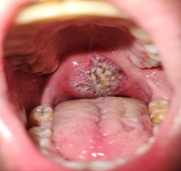

The first case concerns a 53 years old male patient with no specific history admitted to the emergency for recent dysphagia complicated 2 days ago with complete aphagia as well as recurrent episodes of dyspnea, clinical exam revealed tonsillar mass obstructing the oropharynx the patient underwent tracheostomy as well as gastrostomy. Biopsy revealed diffuse large B-Cell lymphoma of the oropharynx, TEP scan was made and reveals no metastasis. This patient was managed successfully with 7 of Rituximab, Cyclophosphamide, Doxorubicine Vincristine, and prednisone (RCHOP) regimen the chemotherapy was complicated with sensoneurinal hearing loss due to ototoxicity tracheostomy and gastrostomy were successfully removed.

Figure 1: Clinical Aspect of case 1 and a cervical scan showing a left tonsillar mass obstructing the oropharynx